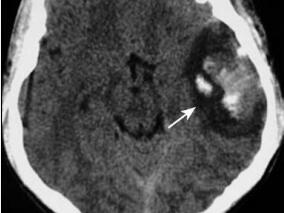

1小时条评论1 病例简介 患者男,68岁,因突发右侧肢体活动不灵伴言语不清2小时于2008年12月7日收入我院神经内科。起病前2小时有反复扛重物史。既往无高血压、糖尿病及冠状动脉粥样硬化性心脏病史。查体:血压120/80mmHg,颈总动脉、椎动脉、锁骨下动脉听诊区未闻及杂音。右侧中...